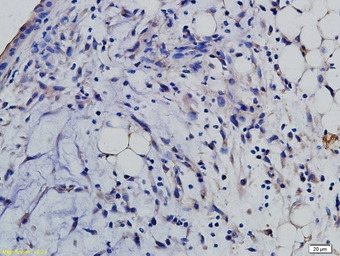

IHC-P analysis of mouse renal tubular endothelial tissue using GTX60322 SLAMF6 antibody.